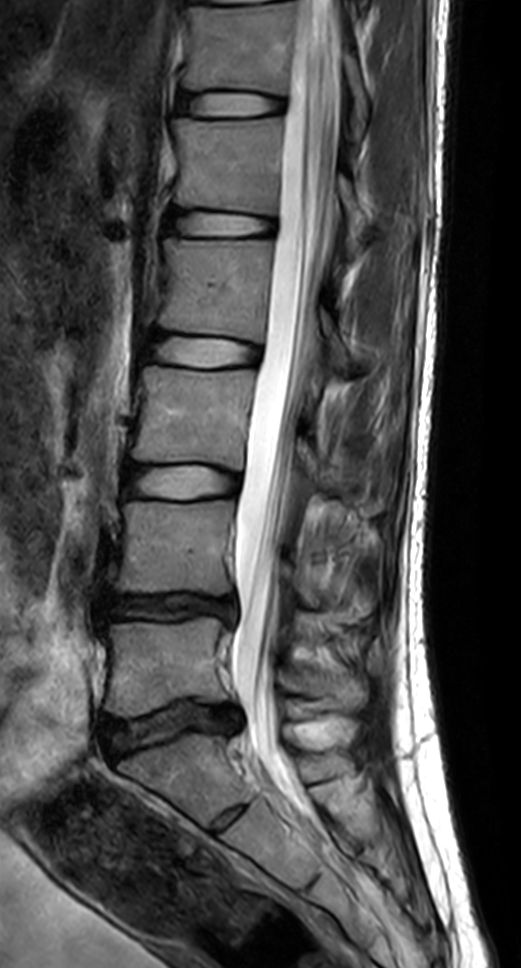

Sagittal T2w TSE

Sagittal PDw TSE

Sagittal T1w FLAIR